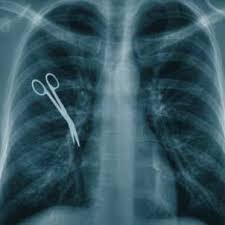

The most frequent error in medicine

The Institute of Medicine, in its seminal report "To Err is Human," defines a medical error as a "wrong plan" or a failure of a planned action to be completed.